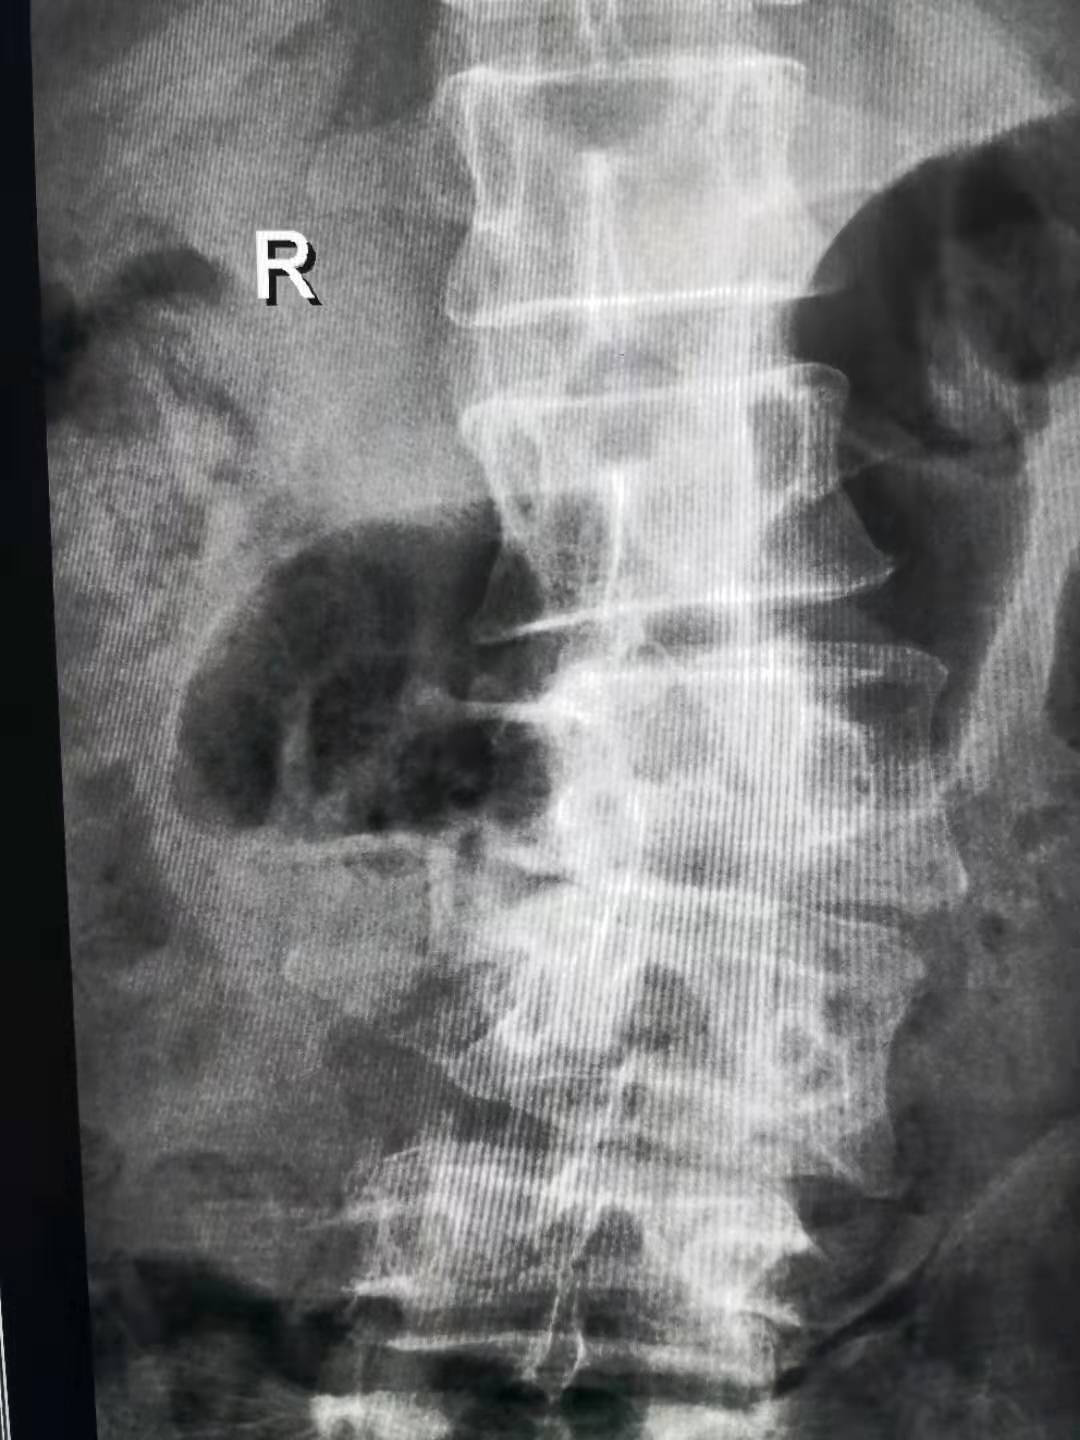

患者张女士,因“腰痛伴间歇性跛行、左下肢疼痛麻木3年,加重10余天”慕名来我院就诊。门诊查体:患者间歇性跛行脊柱外观肋弓下左侧凸畸形,腰椎L4/5处压痛。磁共振辅助检查示:腰椎退行性变 L2-L5椎体左侧凸畸形并椎间隙变窄,L4/5椎管严重狭窄。遂收入骨二科住院治疗。